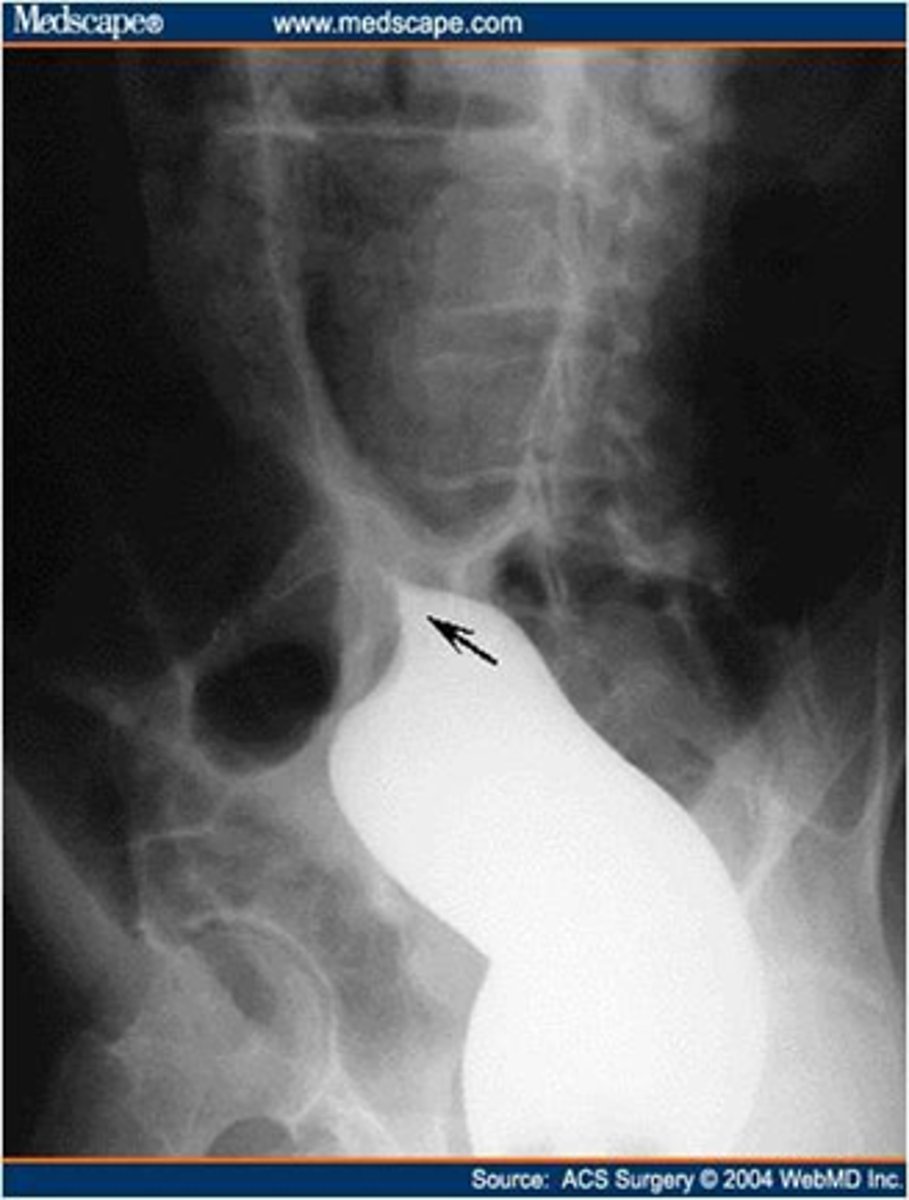

Cricopharyngeal achalasia/Zenker's diverticulum

rare clinical entity in which upper esophageal sphincter (cricopharyngeus) does not open adequately during swallowing leading to dysphagia.

Diverticulum of the mucosa of the pharynx just above the cricopharyngeal muscle.

Zenker's diverticulum